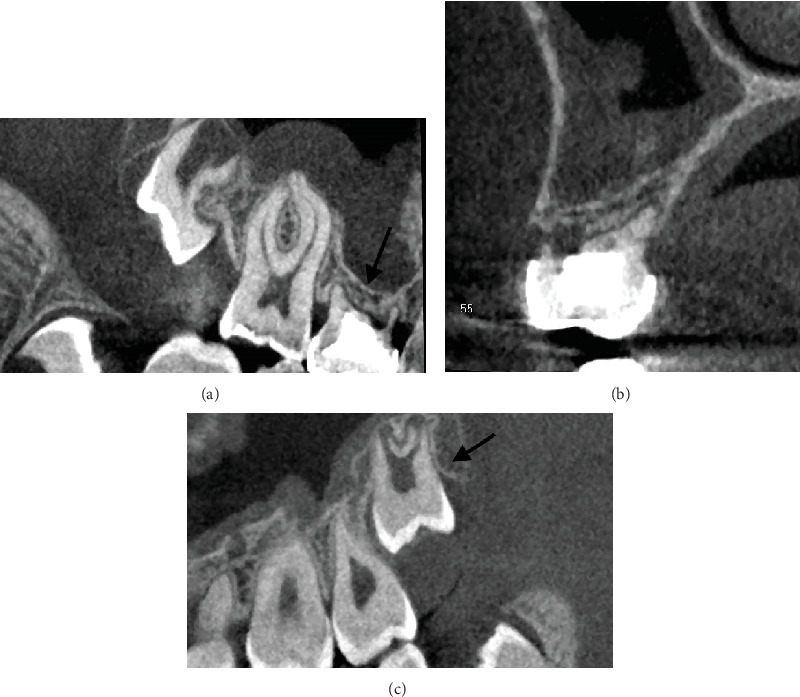

本病例报告报告了由于受术者骨容量不足,牙齿移植和无移植物窦提升是如何结合的。一颗未出牙的智齿被自动移植以取代缺失的上前磨牙。首先,将供牙暴露并轻轻移动。在受体部位,上颌窦下有一薄层骨。侧窗技术用于窦内提升。在提升窦底粘膜后,准备骨以匹配供体牙的尺寸。粘膜轻度穿孔。供体牙移至受体位置,颊根部分骨覆盖缺失。移植的牙齿用缝线固定。在4年的随访对照中,移植牙完全萌出,无任何临床或影像学病理征象。如果移植供牙的牙周韧带处理得当,可以保存和促进牙槽骨的生长。在随访中,供体牙的牙根周围明显形成了新骨。在上颌前磨牙区成功移植发育中的牙齿是可能的,尽管最初的骨容量不足。

This case report reports how tooth transplantation and a graft-free sinus lift were combined due to insufficient bone volume at the recipient site. An unerupted wisdom tooth was autotransplanted to replace a missing upper premolar. First, the donor tooth was exposed and gently mobilized. At the recipient site, there was a thin layer of bone under the maxillary sinus. The lateral window technique was used in the sinus lift. After elevating the mucous membrane of the sinus floor, the bone was prepared to match the measures of the donor tooth. The mucous membrane was slightly perforated. The donor tooth was moved to the recipient site, and the buccal root partially lacked bony coverage. The transplanted tooth was fixated with sutures. At the 4-year follow-up control, the transplanted tooth was fully erupted without any clinical or radiographical signs of pathology. If the periodontal ligament of the transplanted donor tooth is delicately handled, it can preserve and facilitate the growth of the alveolar bone. During follow-up, it was obvious that new bone had formed around the roots of the donor tooth. It is possible to successfully transplant a developing tooth in the maxillary premolar region, although the initial bone volume is insufficient.